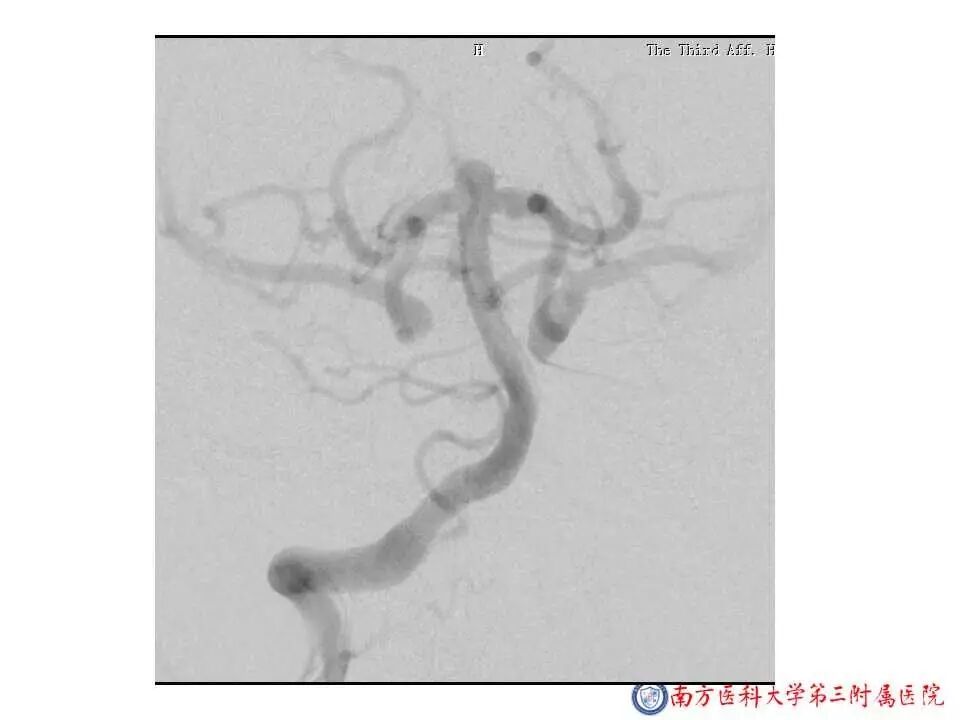

今天为大家分享的是“强生医疗CNV-神经介入专栏”第二十五期,由南方医科大学第三附属医院神经外科主任黄理金教授带来的“Enterprise支架辅助栓塞动脉瘤的优势”精彩讲课视频及PPT,欢迎观看。文章仅代表作者个人观点,如有不同见解,欢迎同道斧正!